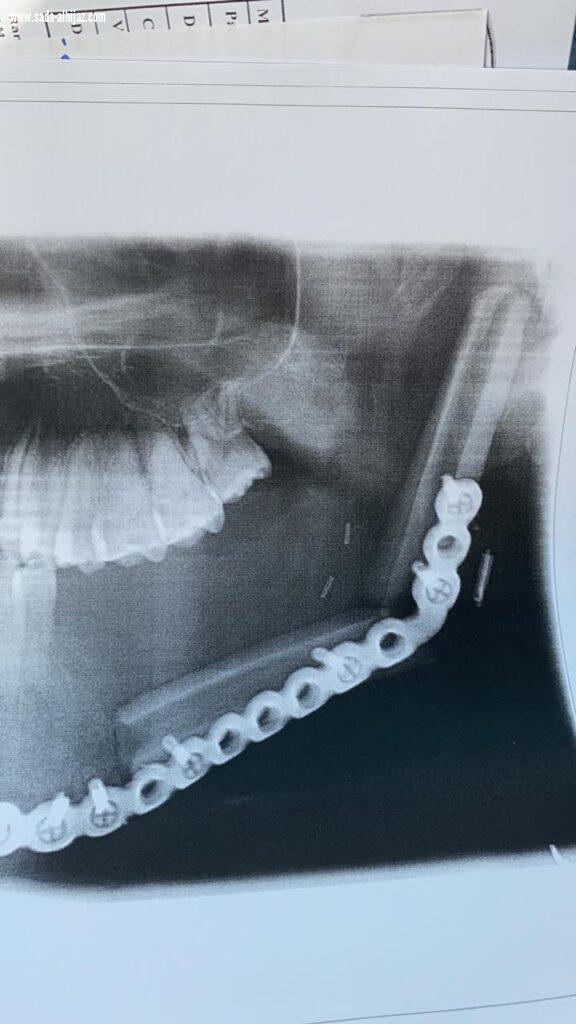

استئصال ورم وإعادة ترميم فك في ثلاث عمليات بمستشفى الملك فهد بالمدينة المنورة

المدينة المنورة - عبدالله الحايطي نجح مستشفى الملك فهد بالمدينة المنورة -بفضل الله- في استئصال ورم من فك مريض في العقد الثالث من العمر وإعادة ترميم عظام الفك باستخدام عظام الساق عن طريق جراحة ميكروسكوبيه . وكان المريض يعاني من وجود ورم في الفك الأيسر أدى إلى تآكل جزء كبير من عظمة الفك وبعد عمل الأشعة والفحوصات اللازمة ودراسة الحالة وعمل الإجراءات لتجهيز المريض إلى غرفة العمليات لترميم الفك المتآكل قام الفريق بإجراء العملية استمرت أكثر من 10 ساعات متواصلة لحصد جزء من عظام الساق مع الشرايين والأوردة الخاصة به عن طريق جراحة ميكروسكوبيه معقدة, ثم إعادة تشكيل هذا الجزء من العظام ليماثل الجزء المستأصل من عظام الفك وتثبيته بشرائح معدنية للحفاظ على شكله الجديد واستعادة وظيفته الأساسية, وعاد المريض ولله الحمد لممارسة حياته بصورة طبيعية .